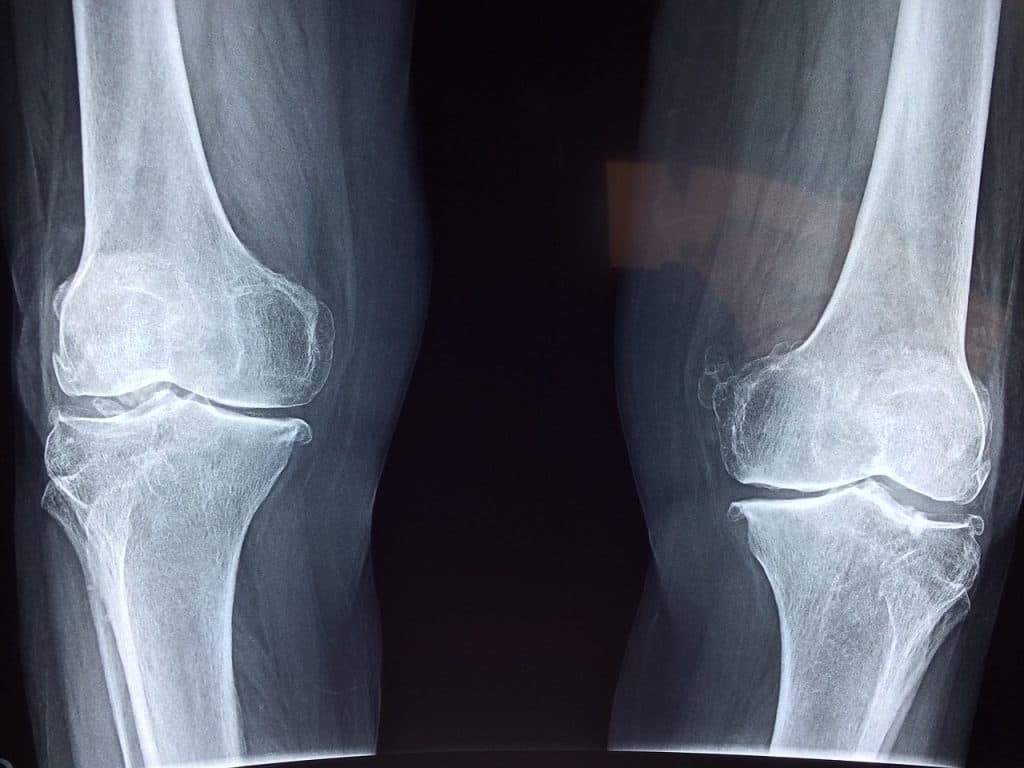

Empecemos por saber qué es el colágeno o colágenos, según sus tipos, son una proteína que posee y se encuentra en nuestro organismo. De hecho, es la más más abundante con una presencia del 20% y 30% de la proteína total que posee un cuerpo adulto. Lo cual, es ideal para mantener nuestras articulaciones en estado óptimo. Aclaremos que, las articulaciones son los puntos en los que se unen dos o más huesos. Como en el caso de las muñecas, codos y rodillas.

Generalmente, estos puntos sufren de severos desgastes y es cuando se originan las lesiones. Por ejemplo, se presentan enfermedades como la artritis y síntomas como: inflamación, fuerte dolor y rigidez en las articulaciones, son sólo algunas dolencias de este tipo. Esto se debe a distintas razones. Entre ellas: el uso de aparatos electrónicos, como el móvil o el mouse del ordenador. Claro está, a largo plazo. También, se presenta la bursitis, que produce una especie de bolsa con líquido en el interior de la articulación y cuya función es protegerla. En casos más aislados, la dislocación. Así que, para todos estos problemas, está indicado el colágeno.